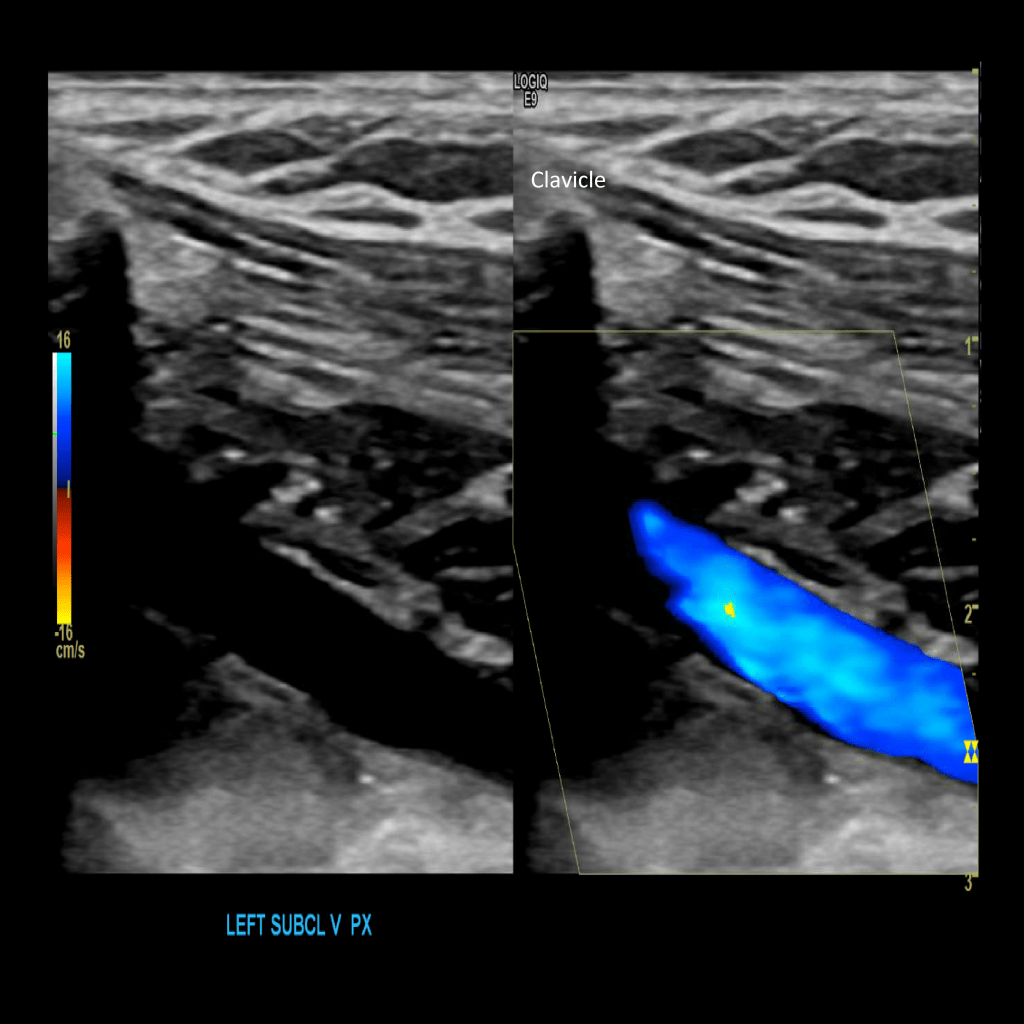

Scan the subclavian vein in grey scale, color doppler and spectral doppler